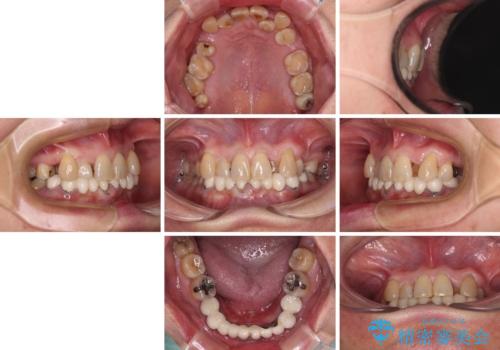

- 常に外れている下顎のブリッジと、前歯のデコボコと色を気にして来院された患者様です。

前歯のデコボコおよび奥歯の咬み合わせを改善するために、上顎左右の小臼歯を欠損スペースを利用して歯列を整え、矯正治療後に気になる上下前歯などをオールセラミッククラウンで美しく仕上げていくこととしました。

色や歯列が整ったことはもちろん満足いただけましたが、上顎の舌側転位していた前歯が綺麗に整ったことで違和感が減ったことを非常に喜んでいらっしゃいました。